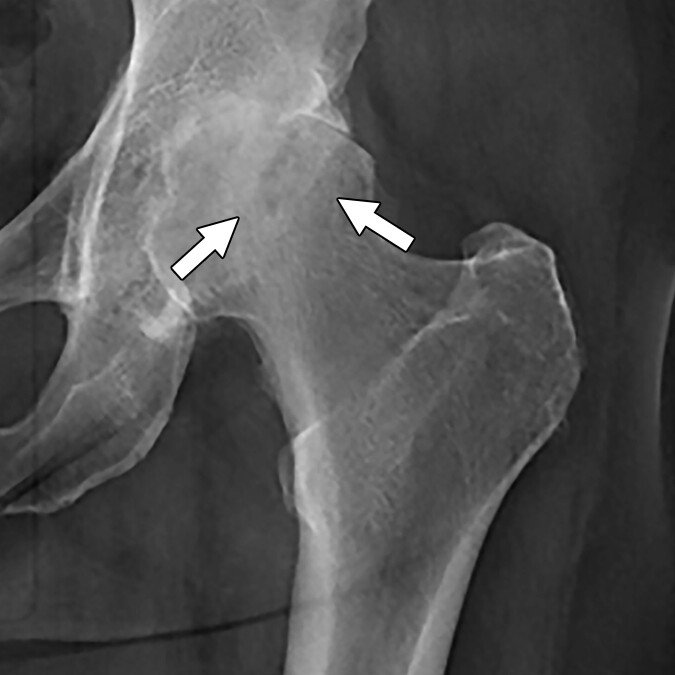

Avascular Necrosis (AVN)

A loss of blood supply to the hip bone leading to joint collapse and chronic pain

Avascular necrosis (AVN), also known as osteonecrosis, is a serious condition that occurs when the blood supply to a section of bone is disrupted. In the hip, this typically affects the femoral head, the ball-shaped part of the thigh bone that fits into the hip socket. Without adequate blood flow, the bone tissue begins to die, which can cause the femoral head to weaken, flatten, and eventually collapse.

Avascular necrosis (AVN), also known as osteonecrosis, is a condition that occurs when the blood supply to the femoral head (the ball of the hip joint) becomes disrupted. Without adequate blood flow, the bone tissue begins to die, leading to the collapse of the femoral head, joint deterioration, and eventually, arthritis. The hip is the most commonly affected joint in AVN, although other joints such as the shoulder or knee may also be involved.

hip osteonecrosis